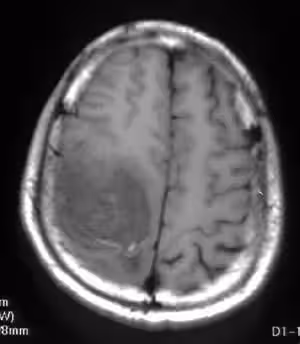

一次例行健康檢查後,醫生告訴何阿嬤,原來,這個寶寶患有重度身心障礙,除腦水腫外,還患有癲癇、過動、斜視等問題。